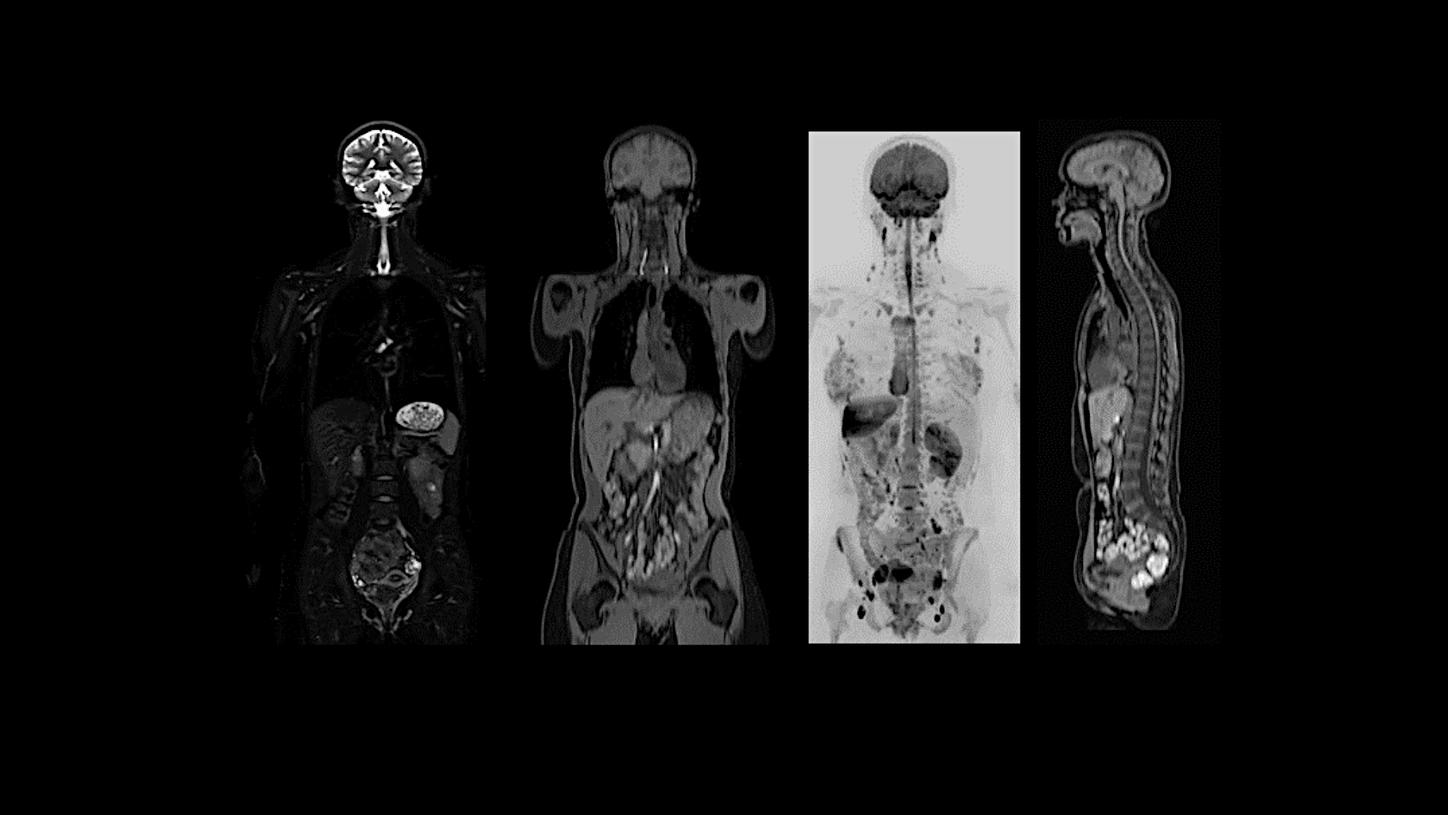

MAGNETOM Flow. Platform is designed to deliver highest-quality imaging for every clinical discipline. From routine imaging and screening to advanced imaging, from head to toe and from cardiac to oncology cases, it is planned to adapt to a wide range of imaging needs. Regardless of the type of institution, throughput demand, or clinical specialty, MAGNETOM Flow. Platform will empower you to achieve clinical excellence.